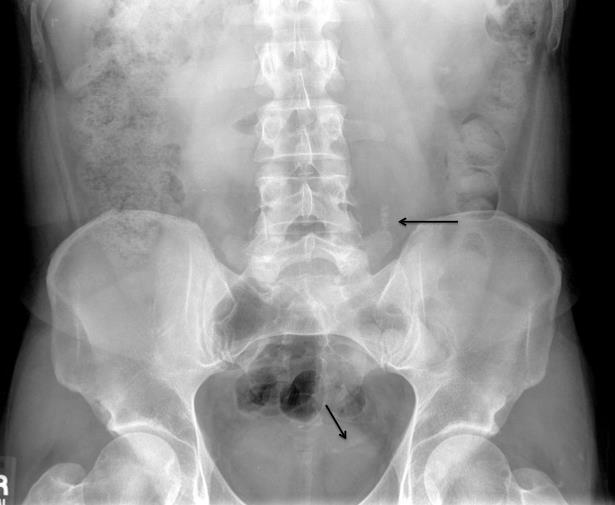

Persistent pain after lithotripsy.